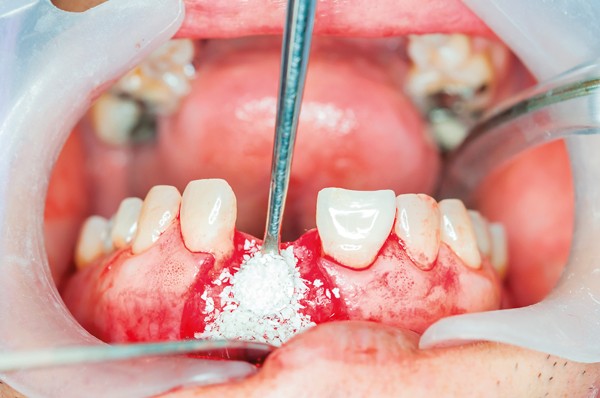

How Is Socket Preservation Performed?

After the tooth is gently removed, the empty socket is carefully cleaned and filled with a bone grafting material. This material may come from the patient’s own body, a donor source, or synthetic alternatives. Once in place, the graft is typically covered with a protective membrane and sutured to secure the area.

The healing process usually takes a few months, during which the grafted material helps promote new bone growth and maintain the natural contour of the gum and jawbone. Once healing is complete, the site will be ready for a dental implant or other type of restoration.